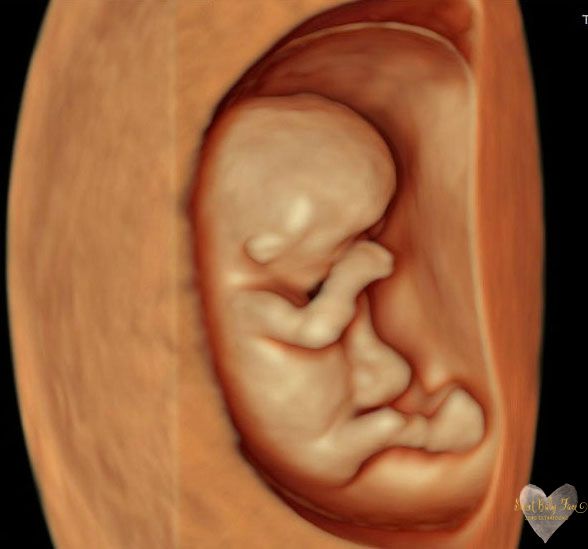

3D/4D/5D Ultrasound Gallery

Take a peek at our Photo Gallery. All of our 2D, 3D, 4D, HD elective ultrasound images are truly ours. They come directly off our machine from our highly trained staff. We can start getting great 3D/4D images as early as 10 weeks!